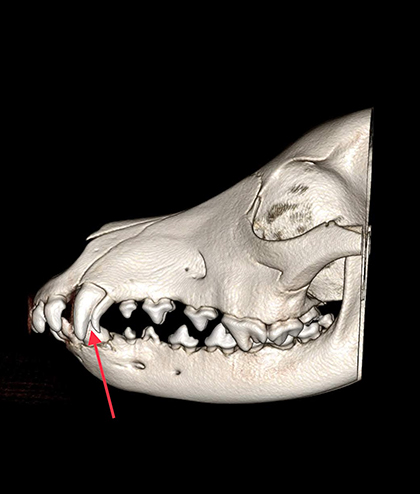

When you think of orthodontics, most people picture metal brackets connected by elastic bands to correct various dental problems, such as a malocclusion (the teeth don’t fit together properly) and crooked teeth. The practice of moving a tooth into a different position in the mouth may sometimes be painful, but the end result can be a prettier smile and a mouth that is healthier and more functional. But why would we fix crooked teeth in a pet?

The answer is: to make a pet’s mouth healthier and less painful. This is a key difference from human orthodontics—we are not aiming for the perfect smile; we are aiming for the most comfortable smile!

- Odontoplasty and dentinal sealants (lightly blunting the tip of the tooth)

- Interceptive orthodontics—extracting select teeth

- Crown amputation with vital pulp treatment

- Inclined plane and other custom-made retainers or spacers

- Active-force orthodontics (brackets with elastic bands)